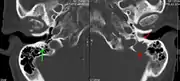

The diagnostic examination of a person with suspected multiple myeloma typically includes a skeletal survey. This is a series of X-rays of the skull, axial skeleton, and proximal long bones. Myeloma activity sometimes appears as "lytic lesions" (with local disappearance of normal bone due to resorption) or as "punched-out lesions" on the skull X-ray ("raindrop skull"). Lesions may also be sclerotic, which is seen as radiodense.[70] Overall, the radiodensity of myeloma is between −30 and 120 Hounsfield units (HU).[71] Magnetic resonance imaging is more sensitive than simple X-rays in the detection of lytic lesions, and may supersede a skeletal survey, especially when vertebral disease is suspected. Occasionally, a CT scan is performed to measure the size of soft-tissue plasmacytomas. Nuclear Medicine Bone scans are typically not of any additional value in the workup of people with myeloma (no new bone formation; lytic lesions not well visualized on nuclear bone scan).

- A CT of the brain revealed a lytic lesion in the left temporal bone (right side of image), and petrous temporal bones involving the mastoid segment of the facial nerve canal. Red arrows: lesion; green arrow: normal contralateral facial nerve canal. The lesions are consistent with a myeloma deposit.